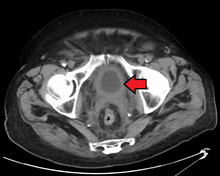

- N1 Metastasis in a single lymph node 2 cm or less in greatest dimension

- N2 Metastasis in a single lymph node more than 2 cm but not more than 5 cm in greatest dimension,or multiple lymph nodes, none more than 5 cm in greatest dimension

- N3 Metastasis in a lymph node more than 5 cm in greatest dimension